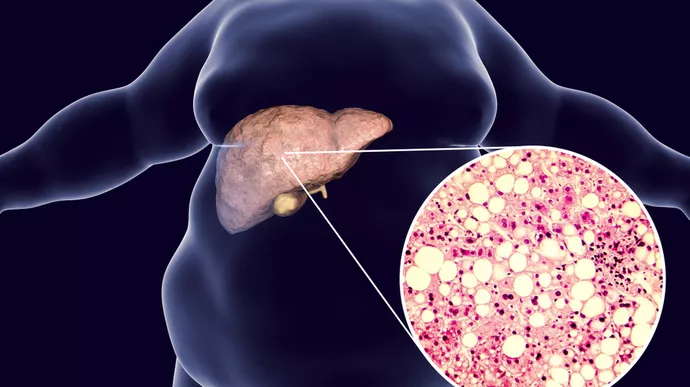

Fatty liver disease occurs when fat accumulates in liver cells. Normally, a small amount of fat is present in the liver. However, when fat becomes excessive, problems may begin.

In most cases today, NAFLD is more common. Although early stages may not show symptoms, proper evaluation by the best doctor for fatty liver in Bhopal helps detect the problem early.

- Obesity

In addition, sudden weight gain may also contribute. Because lifestyle plays a major role, treatment focuses not only on medicines but also on habit changes.